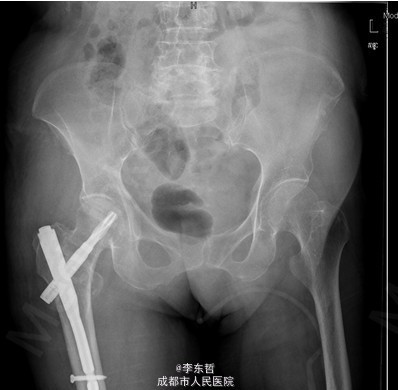

初步诊断:1、右股骨转子间骨折(Evans III型);2、骨质疏松症。 诊疗计划:1、向患者及家属交待病情及注意事项。2、向上级医生汇报患者病情。3、完善术前相关检查。4、给予皮肤牵引、抬高患肢等对症处理。5、拟手术治疗。6、密切观察病情变化,根据病情及时处理。

随访无特殊